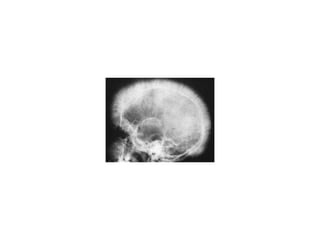

• A “crew cut” skull x-ray appearance may be seen

THALASSEMIAS • A WIDEVARIETY of diseases involving GLOBIN synthesis, COMPLEX genetics • Alpha or beta chains deficient synthesis involved • Often termed MAJOR or MINOR, depending on severity, silent carriers and “traits” are seen • HEMOLYSIS is uniformly a feature, a microcytic anemia • A “crew cut” skull x-ray appearance may be seen

• #29 Note the “spiculated” appearance of the outer table of the skull due to extreme erythroid hyperplasia!